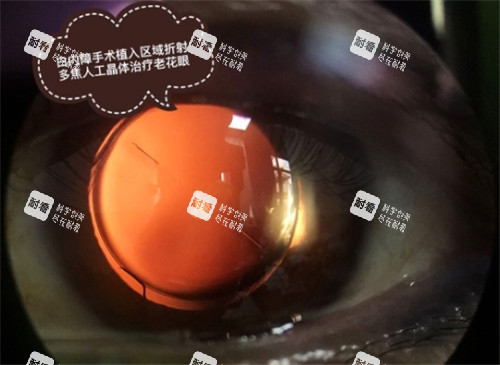

需要注意的是,飛秒激光、多焦點(diǎn)晶體等高端項(xiàng)目是需要全額自付的。

在選擇手術(shù)方案時(shí),患者要根據(jù)自己的經(jīng)濟(jì)狀況和實(shí)際需求進(jìn)行合理選擇,避免因?yàn)檫x擇高端項(xiàng)目而增加不必要的經(jīng)濟(jì)負(fù)擔(dān)。